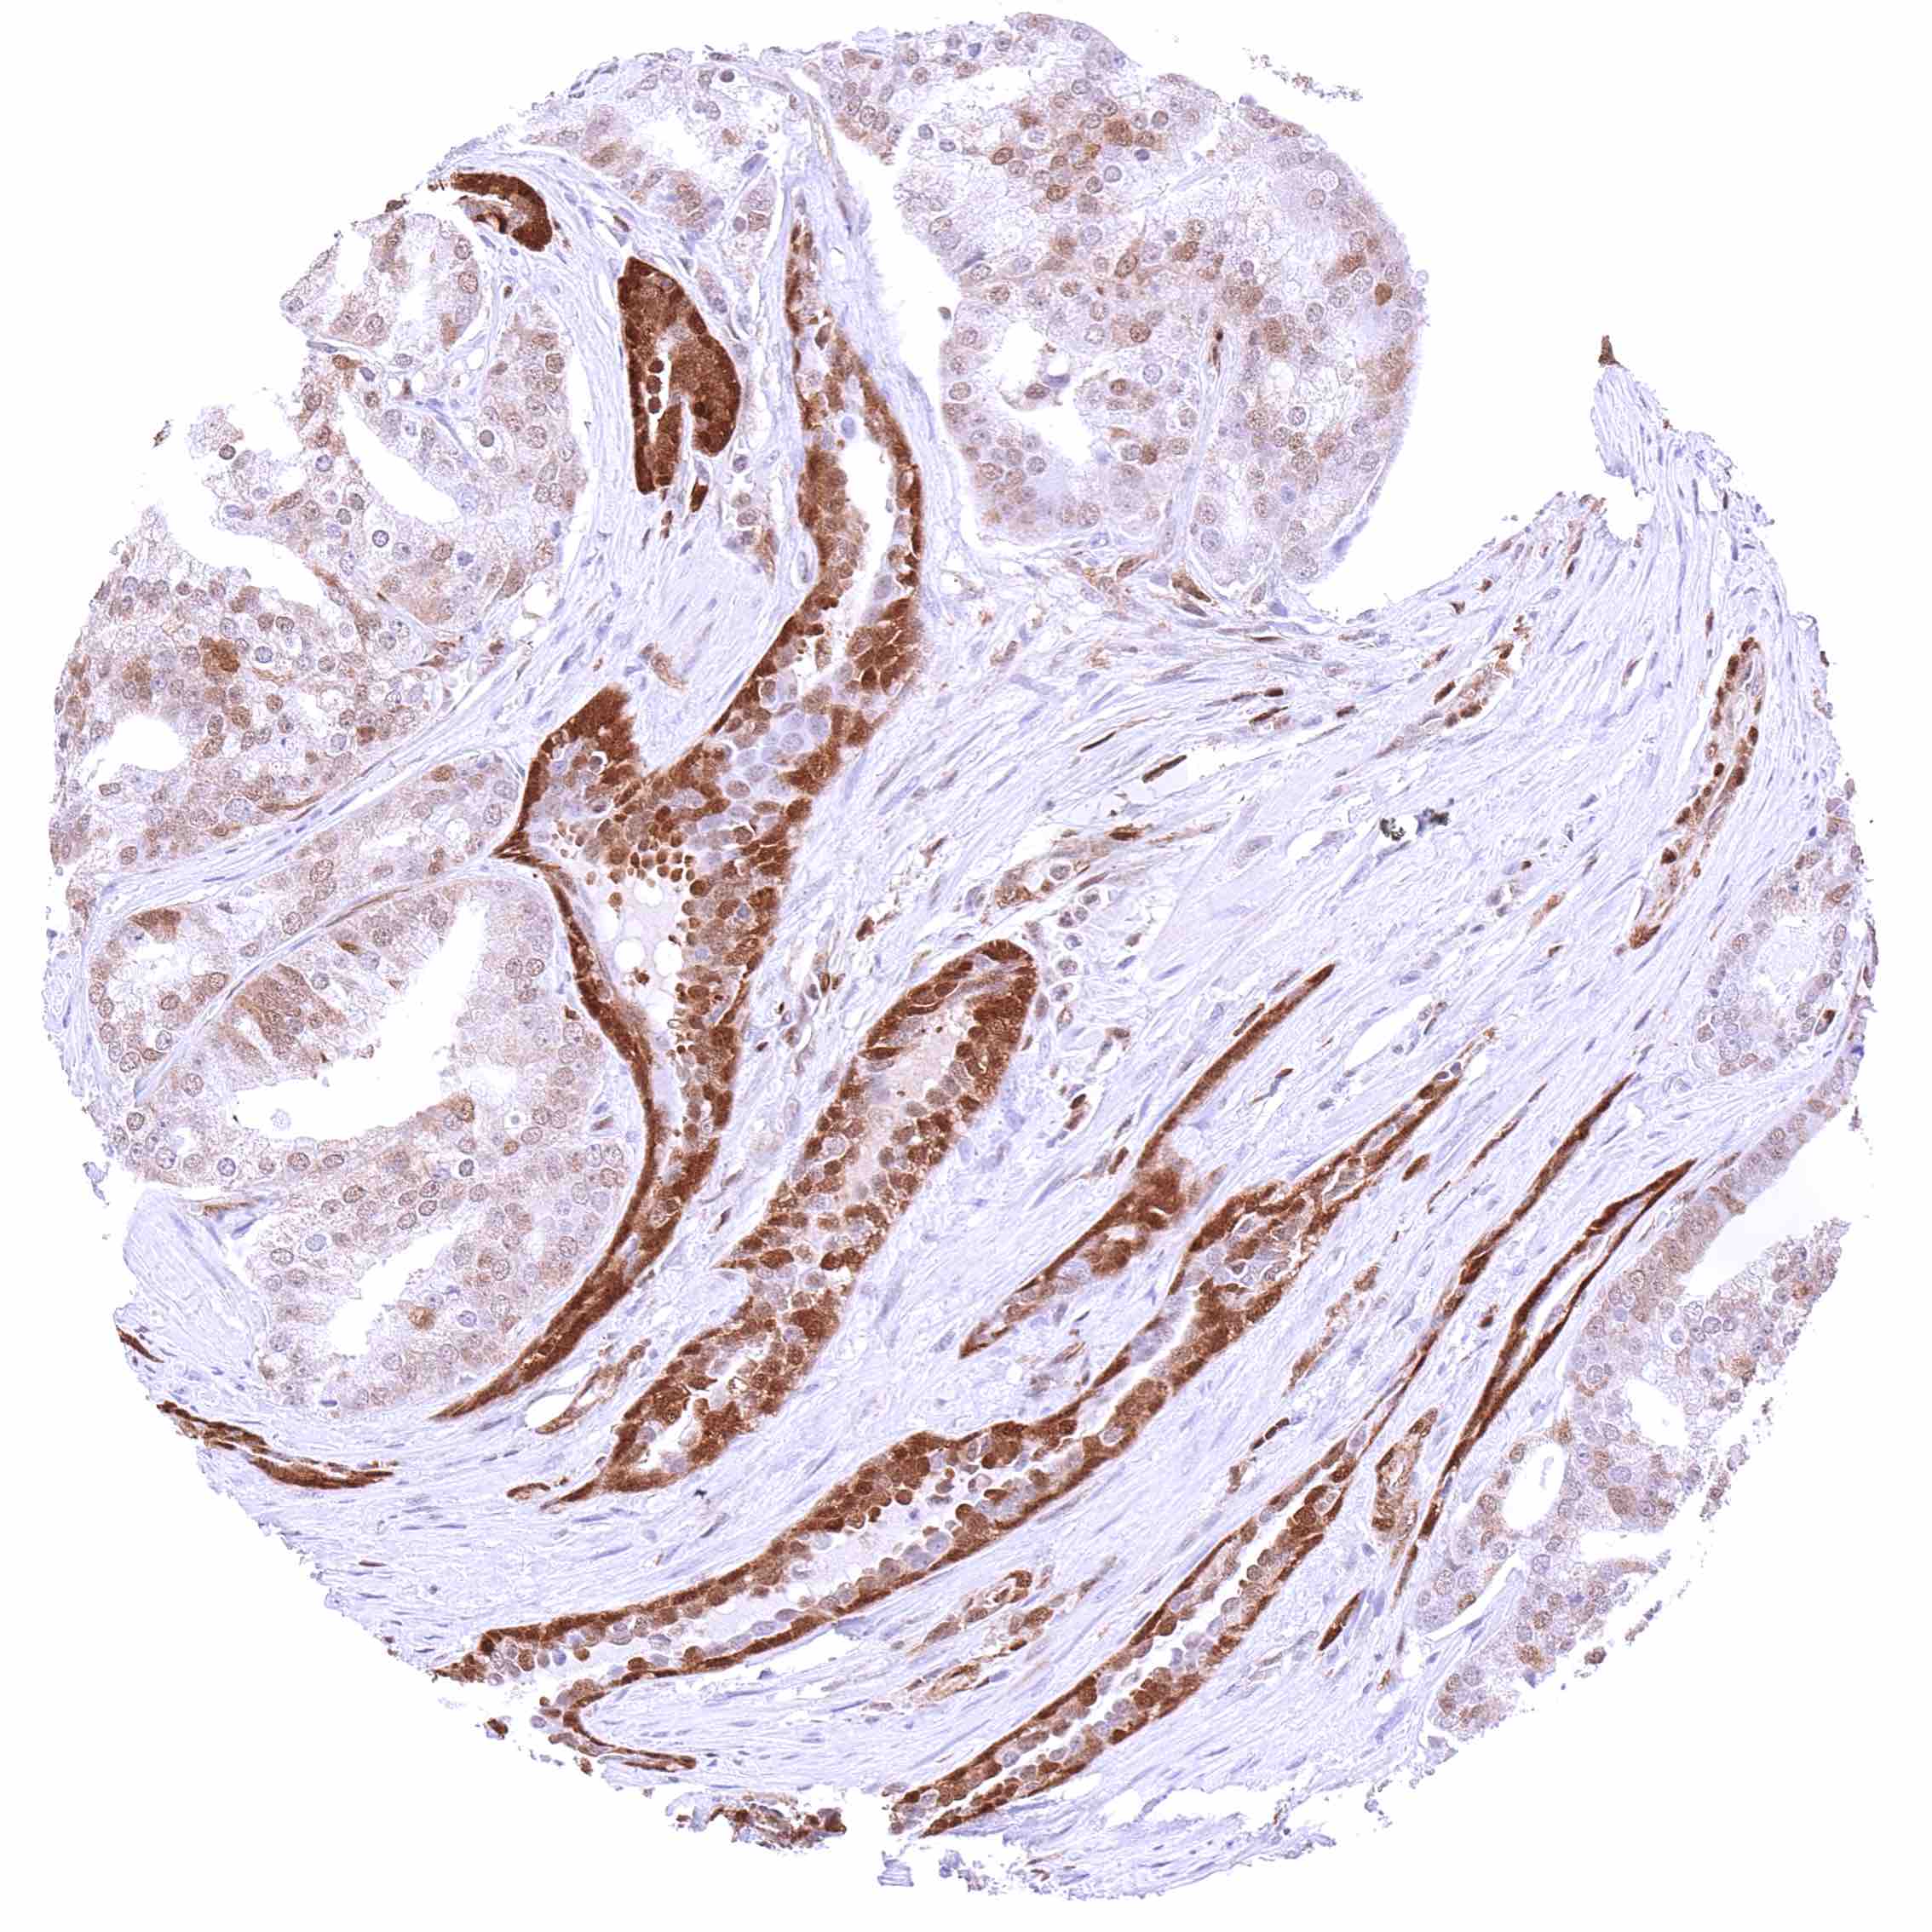

Uterus, cervix – Squamous cell carcinoma with a variable, weak to strong, predominantly cytoplasmic p27 staining of tumor cells.